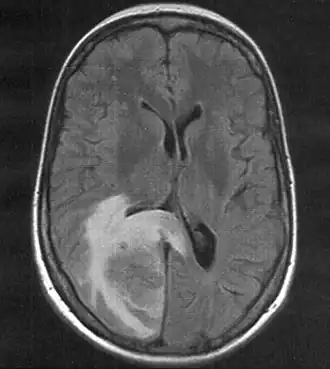

![]() | |

Skull MRI (T2 flair) of a brain metastasis with accompanying edema | |